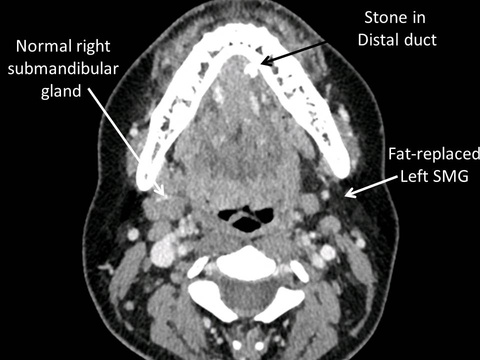

In the absence of bacterial contamination chronic obstruction to outflow of saliva from a major salivary gland often results in its involution as a non-functional asymptomatic remnant of a gland. Although the goal of sialendoscopy-assisted gland-preserving surgery in the management of salivary obstruction from stones and strictures is relief of symptoms and restoration of normal salivary flow, sometimes these dual goals are not achieved. Relief of painful swelling of salivary glands may occur without normal production of saliva when the gland atrophies or involute. Examples of cases are listed below:

44 year old with intermittent swelling of the left submandibular gland for 15 years without treatment to date: